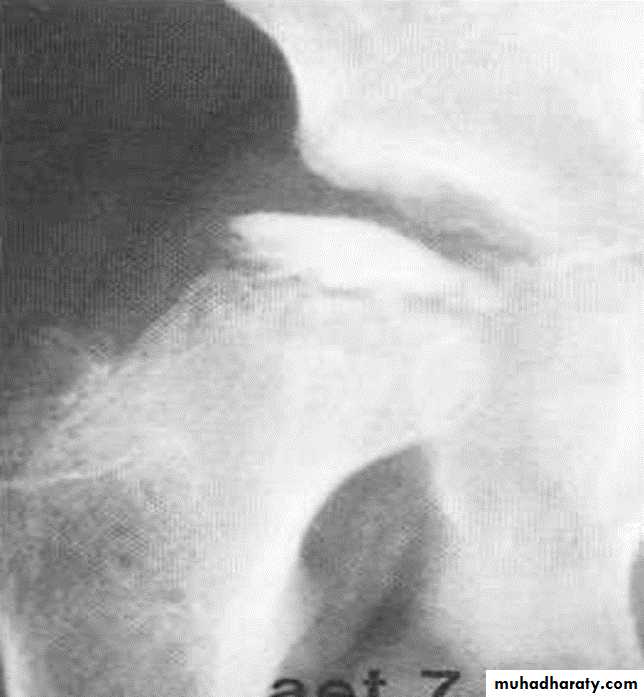

OSTEONECROSIS

Osteonecrosis (avascular necrosis, ischemic necrosis, aseptic necrosis) may be caused by two mechanisms:* Interruption of arterial supply

* Intra/extraosseous venous insufficiency

The pathophysiology of all osteonecrosis is the same:

Ischemia > revascularization >repair > deformity> osteoarthrosisRadiological findings:

Findings lag several months behind time of injury.

These findings include areas of radiolucency, fissuring , fragmentation , bone collapse and condensation , end with dense and flat bone with loss of bone contour and secondary osteoarthritis

Legg-Calve-Perthes disease : osteochodrosis of the femur headUsually affects 5-10 years , started as hip pain , if not treated it will ends with mushroom deformity due to neglected and untreated perthis seen later on and is liable for early OA chnges .

Perthes' disease. A series of radiographs showing the stages of healing. (A) The initial radiograph shows a flattened, sclerotic femoral head

The left femoral neck is broadened, the metaphysis sclerotic

with focal areas of lucency, the growth plate irregular and the femoral headflattened and sclerotic. It is uncovered laterally. The joint space appears

widened